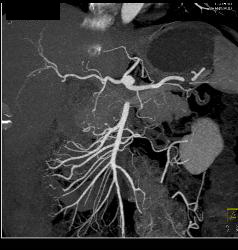

Fibromuscular Dysplasia (FMD) of Right Renal Artery the Mesenteric Vessels Were Normal